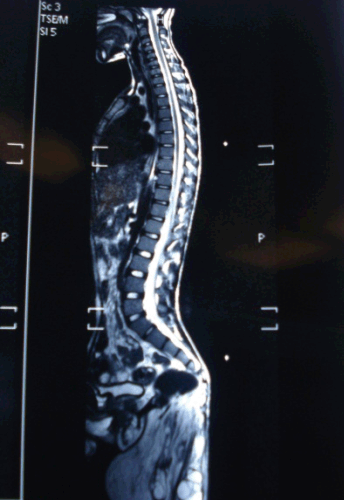

A 16-year-old boy presented in the outdoor department of our institute with history of malformation attached to his lower back since birth. The boy was born 16 years back, with history of vaginal breech delivery at home with prolonged labor. At birth the infant had irregular mass in his lower back covered by a membrane which ruptured in few weeks to reveal a malformation initially interpreted as supernumerary limbs which has grown in size with the growth of child . The boy had difficulty in performing daily routine activities including unable to dress properly and lie in supine. The patient was of average built and nutrition; vitals were normal and had mild pallor. The sacral portion of the spine was deformed protruding backward at an angle of about 45 degrees, underneath to which was attached a malformation. This malformed structure had well appreciable lower limbs with toes and nails although no movements were recorded in these limbs either spontaneous or upon stimulation. There were nipples, hairs, and pubic hair area and skin ulceration of size 6x7 cm noticed over malformation (Figure 1). The patient was undertaken for detailed radiological examination including ultrasound abdomen, Contrast enhanced computed tomography of abdomen and MRI spine. These investigations did not reveal any gross communication of malformation with the abdominal cavity or spine of the patient (Figure 2). The surgical excision of the malformation was performed without any significant complication. The malformation was mostly exterior with extension in the presacral space displacing sacrum posterior, there was no direct communication in the abdomen or spinal canal of the patient and gluteal muscles of the patient were ill developed. The main vascular supply of the malformation was from middle sacral artery of the patient.

Figure 2: MRI showing attachment of parasite in presacral space.

Figure 3: MRI showing attachment of parasite in presacral space.